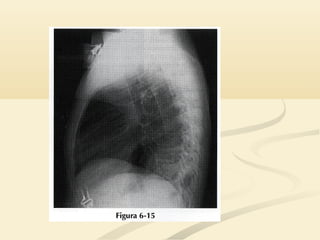

 Existe un signo de la silueta “normal” en la radiografía lateral.Existe un signo de la silueta “normal” en la radiografía lateral.

 El corazón está situado predominantemente sobre elEl corazón está situado predominantemente sobre el

hemidiafragma izquierdo anterior. Ambas estructuras tienenhemidiafragma izquierdo anterior. Ambas estructuras tienen

densidad agua; por lo tanto la parte anterior del hemidiafragmadensidad agua; por lo tanto la parte anterior del hemidiafragma

izquierdo no suele ser visible.izquierdo no suele ser visible.

 En la radiografía lateral, el hemidiafragma derecho esEn la radiografía lateral, el hemidiafragma derecho es

visible a través del corazón porque está en contacto convisible a través del corazón porque está en contacto con

pulmón aireado.pulmón aireado.

 Esto ayuda a distinguir el hemidifragma izquierdo delEsto ayuda a distinguir el hemidifragma izquierdo del

derecho en la radiografía lateralderecho en la radiografía lateral

 Existe unsigno de la silueta “normal” en la radiografía lateral.Existe un signo de la silueta “normal” en la radiografía lateral.  El corazón está situado predominantemente sobre elEl corazón está situado predominantemente sobre el hemidiafragma izquierdo anterior. Ambas estructuras tienenhemidiafragma izquierdo anterior. Ambas estructuras tienen densidad agua; por lo tanto la parte anterior del hemidiafragmadensidad agua; por lo tanto la parte anterior del hemidiafragma izquierdo no suele ser visible.izquierdo no suele ser visible.

 En laradiografía lateral, el hemidiafragma derecho esEn la radiografía lateral, el hemidiafragma derecho es visible a través del corazón porque está en contacto convisible a través del corazón porque está en contacto con pulmón aireado.pulmón aireado.  Esto ayuda a distinguir el hemidifragma izquierdo delEsto ayuda a distinguir el hemidifragma izquierdo del derecho en la radiografía lateralderecho en la radiografía lateral